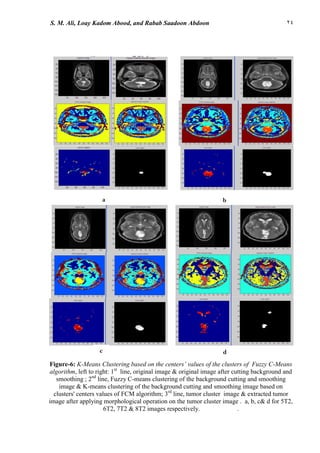

s technique is implemented on the input MRIs (with cluster number equals to 6 ) . The

segmented image including the cluster of the tumor was selected and opening morphological

operation with structure element of shape disk (four pixels diameter) for images 5T2, 6T2,

7T2 & 8T2. The resulted image is then convoluted with the original image to acquire the

image of the tumor region, shown in fig-5. The tumor region's surface area is listed in Table-1.

Figure-5: Fuzzy C-Means Clustering, left to right: 1st

line , original image & original image

after cutting background and smoothing; 2nd

line Fuzzy C-means clustering of the background

cutting and smoothing image; 3rd

line, tumor cluster image & extracted tumor image after

applying morphological operation on the tumor cluster image. a ,b , c & d for 5T2,6T2,7T2

&8T2 images respectively.